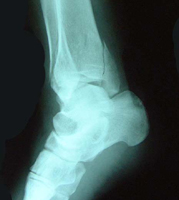

受傷後88日目

写真により骨折部の治癒を認め

受傷後11日目(第2診目)に転位を確認し、末梢骨片に中枢骨片が接合するよう再整復し、固定を行ったことが骨折部の良好な位置関係の維持を可能にしたと考える。

体重負荷を十分な骨癒合が得られるまで禁止することにより、転位の抑制と良好な骨癒合が得られたものと考える。